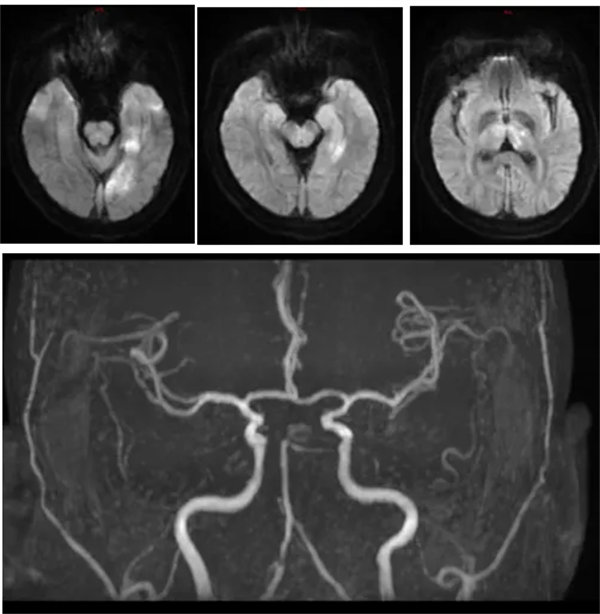

近日,42歲的張先生因突發頭暈、右手無力、視物模糊10小時,意識不清10分鐘,被家屬發現后緊急送至我院急診科,考慮腦卒中收入神經內三科進一步治療,到達科室后患者已神志不清,且伴有呼吸淺快,大小便不能自控。NIHSS評分35分,mrs評分4分;行頭顱DWI提示左側顳枕葉、左側丘腦急性腦梗死;顱腦MRA提示右側大腦后及小腦上動脈未見顯影,左側大腦后動脈P1段明顯變細,遠端閉塞。